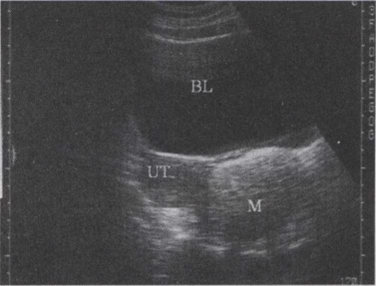

45.如图,女,26岁,无明显不适,盆腔横断面,最可能的诊断是()